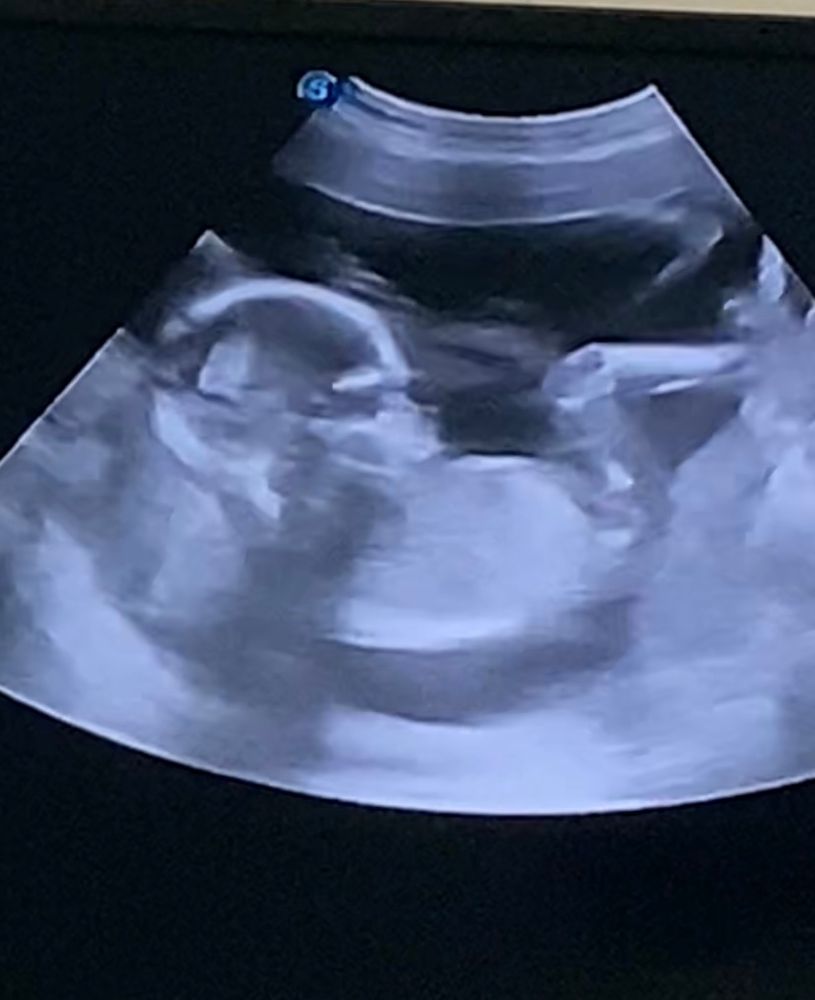

Скажите пожалуйста вы видите здесь пол малыша,тут все виды снизу и один с боку

Череп более мальчуковый,а никаких мужских органов на этих фото не видно.

Да , мальчик

Мальчик

Парнишка